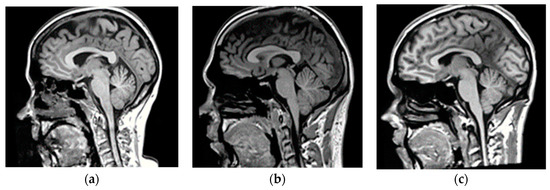

2.2.1. Training Dataset

2.2.2. Validation Dataset